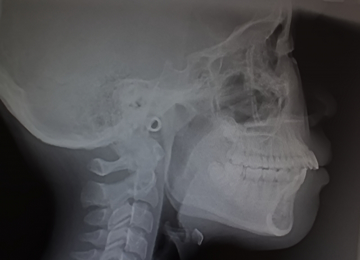

セファロ分析による精密な矯正診断

2)セファロ分析による精密な矯正診断

セファロ分析は、規格化された頭部のレントゲン写真(セファロ)を用いて、顎や歯の骨格的な位置関係を詳しく解析する方法です。成長の状態や不正咬合の状況を客観的に評価できるため、適切な治療計画を立てるうえで欠かせません。定期的な撮影と比較により、治療効果の確認や成長の変化も把握できます。安全で正確な矯正治療の実現に重要な役割を果たします。